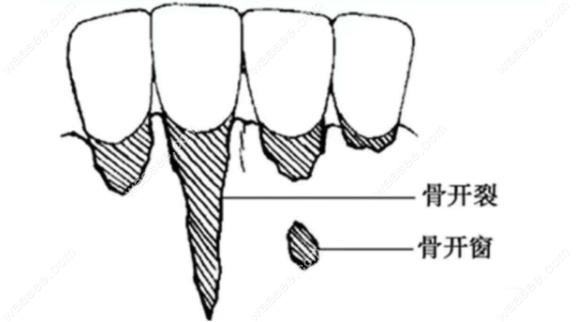

骨开裂和骨开窗图片

骨开窗示意图

正畸形成骨开窗和骨开裂有啥区别?看骨开窗示意图自行判断

骨开窗,骨开裂示意图

正畸形成骨开窗和骨开裂有啥区别?看骨开窗示意图自行判断

骨开窗和骨开裂的对比